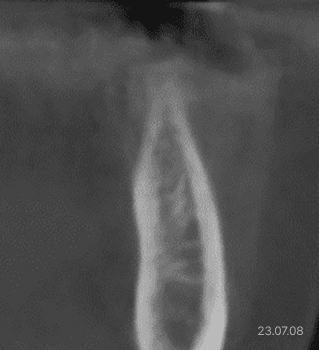

상악동 골이식 전 모습

상악동 골이식 후 모습

상악동 골이식 전 엑스레이

상악동 골이식 후 엑스레이